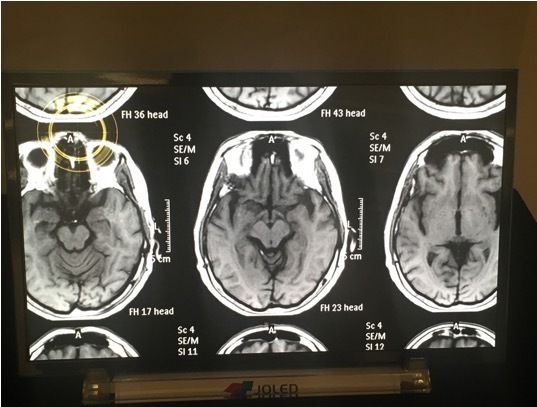

一方、12月5日、JOLEDは21.6インチの有機ELディスプレイの初出荷を発表した。世に初めて印刷方式、3原色独立発光のパネルを用いた有機ELディスプレイは、ソニーの関連会社に納入され、医療用システムの一端を担う。